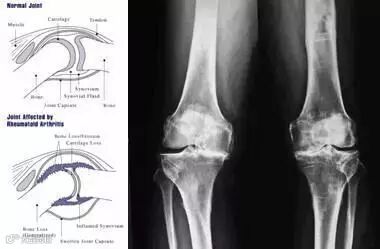

类风湿关节炎(RA)是一种病因未明的慢性、以炎性滑膜炎为主的系统性疾病。其特征是手、足小关节的多关节、对称性、侵袭性关节炎症,经常伴有关节外器官受累及血清类风湿因子阳性,可以导致关节畸形及功能丧失。全球有超过2300万人患有此病,多在中年发作,女性患者数量是男性的3倍。

[临床表现]

(1)晨僵

(2)关节畸形